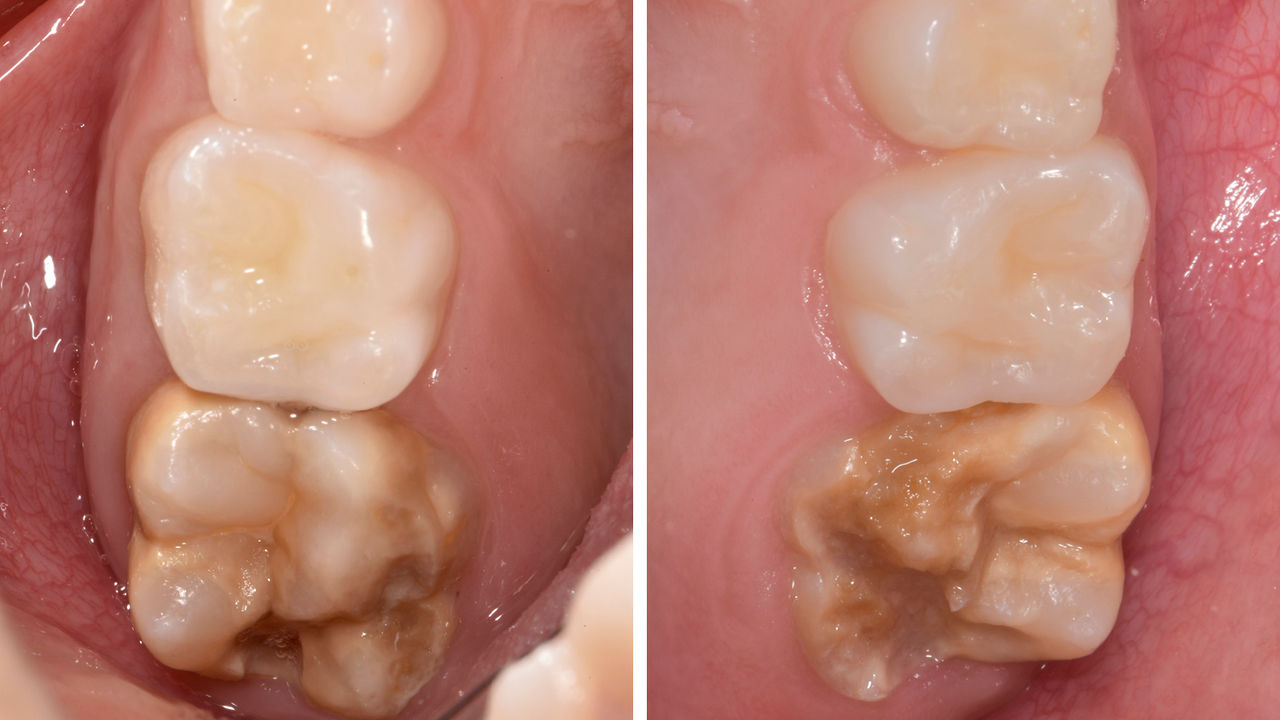

Before: Failed amalgam restoration needing replacement. Patient complaining of sensitivity and tooth presenting multiple cracks.

After: Chairside CAD/CAM partial crown restoration fabricated with CEREC Tessera Advanced Lithium-Disilicate glass ceramic.